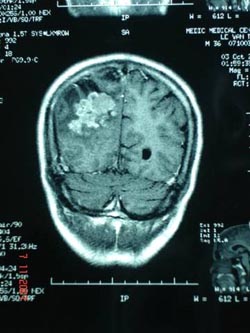

Vào viện ghi nhận: Bệnh nhân tỉnh táo không nhức đầu, không liệt, không nôn, và các dấu hiệu thần kinh cũng như cơ quan khác chưa phát hiện dấu bệnh lý. Bệnh nhân được cho làm các xét nghiệm thăm dò chức năng các cơ quan gan thận phổi tim đều chưa phát hiện dấu bệnh lý. Xét nghiệm HbsAg dương tính (+++). HIV (-). Chụp MRI sọ não cho thấy có thương tổn ở vùng đỉnh chẩm phải (hình 1).

| Hình 1: Thương tổn ap-xe não do nấm dưới hình ảnh MRI |